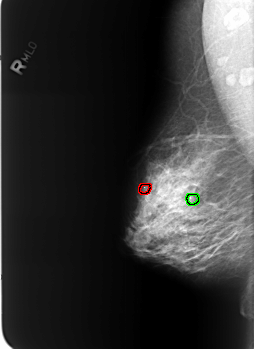

B_3235_1.RIGHT_MLO

FILE: B_3235_1.RIGHT_MLO.OVERLAY

TOTAL_ABNORMALITIES 2

ABNORMALITY 1

LESION_TYPE CALCIFICATION TYPE LUCENT_CENTER DISTRIBUTION N/A

ASSESSMENT 2

SUBTLETY 5

PATHOLOGY BENIGN_WITHOUT_CALLBACK

ABNORMALITY 2